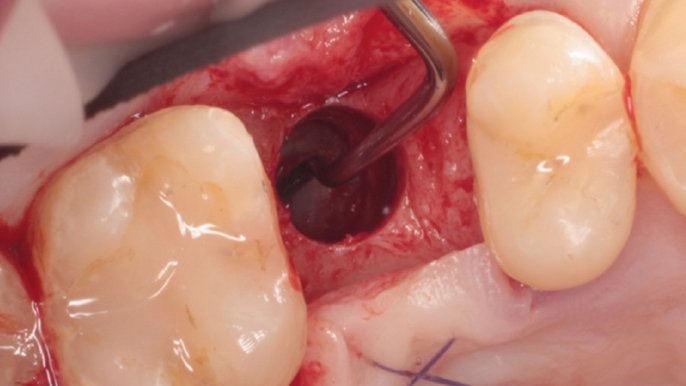

Clinical case: Ridge splitting technique using SmarThor + AnyRidge as expander

- Courtesy of Dr.Kwang-Bum Park, Korea -

AnyRidge, ridge splitting, GBR, Dr. Kwang-Bum Park, mandibular posterior, SmartThor, Mega-Oss, thin ridge, bone regeneration

AnyRidge implant system. SmarThor, Mega-Oss